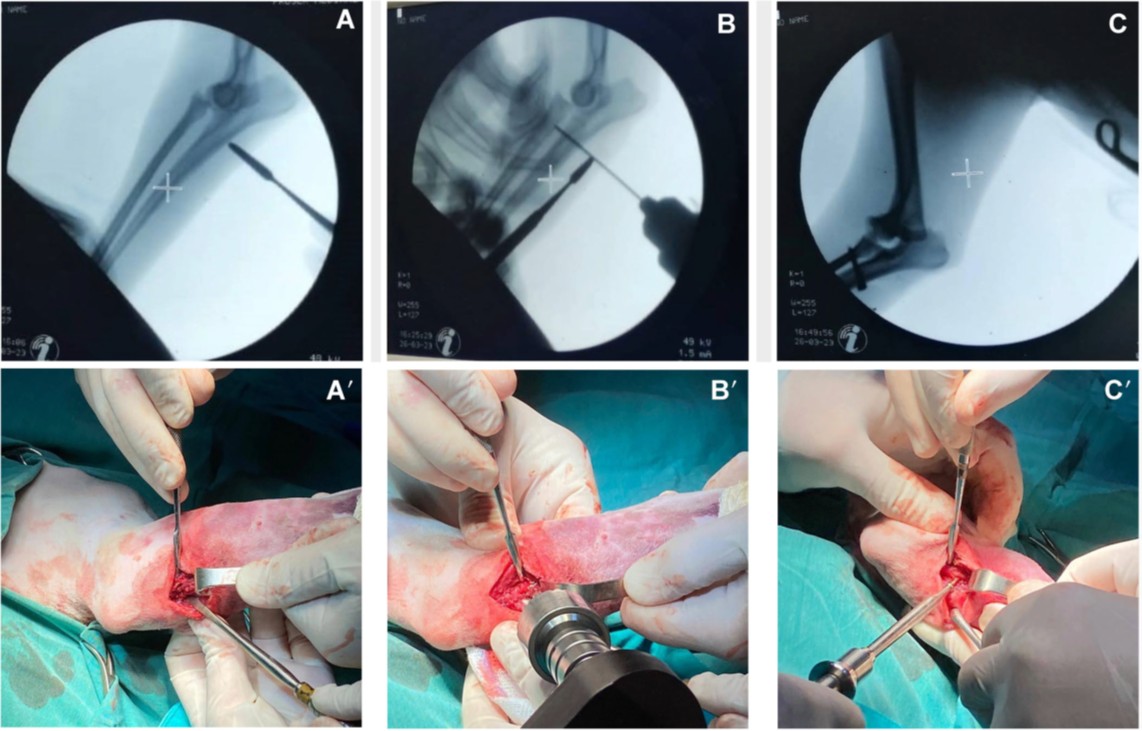

最初在全麻下进行了脱位肘关节的闭合复位。通过牵引、屈曲和内旋,使用Campbell描述的闭合复位技术复位肱桡关节和桡尺关节。在复位过程中,尽管尺骨成功复位到其解剖位置,但桡骨无法重新对齐。桡骨头仍然脱位(下图)。由于肘关节闭合复位失败,计划进行手术治疗。

↑ 闭合复位后肘关节的正侧位(A)和头尾位(B)视图。尺骨已成功复位至其解剖位置;然而,桡骨头仍然脱位。